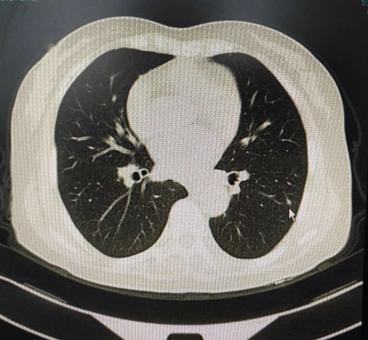

王女士,48岁,半年前当地检查ct发现左肺结节,无明显症状,当时医生嘱3~6个月复查,后来我院查ct,影像及报告见下图